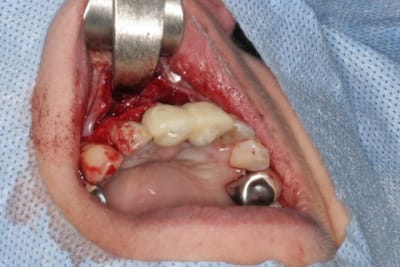

tien, ce matin, extraction de 24/25, curetage méticuleux, forage, comblement du gap, pose des 2 implants qui se sont bloqués à 50Ncm au CA sur les 3 ou 4 mm apicaux, pose des vis de cicat, sutures...35min....tranquille...

un autre cas EII MCI sur 11/21...mais en photos (j'ai aussi la vidéo, faut que je la passe sur youtube)

perso, j'ai totalement switché sur l'interactive

tu auras en plus 2 bonus:

la partie colorée du pilier est clipsée...plus besoin de disque carbo...en plus pour l'empreinte çà permet une empreinte fermée clipée quasi aussi précise qu'une à ciel ouvert...

autre bonus: tes vis ne tomberont plus...il y a de nouveau le filetage dans le moignon (bein oui qui dit conique dit plus de friction...et donc filetage dans la pièce prothétique au cas où...pour les instruments de désinsertions à visser, comme feu le TRLT2 zimmer)